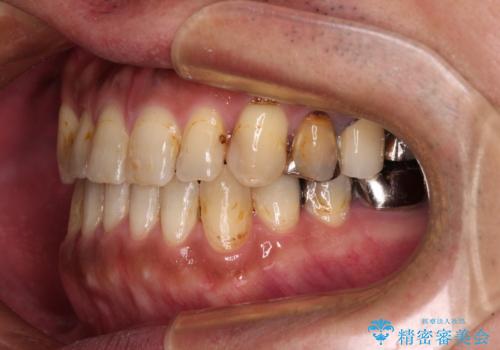

矯正治療後は安定した咬み合わせとなり、顎の違和感がなくなったとのことでした。

今後はむし歯や銀歯を治療していく予定です。